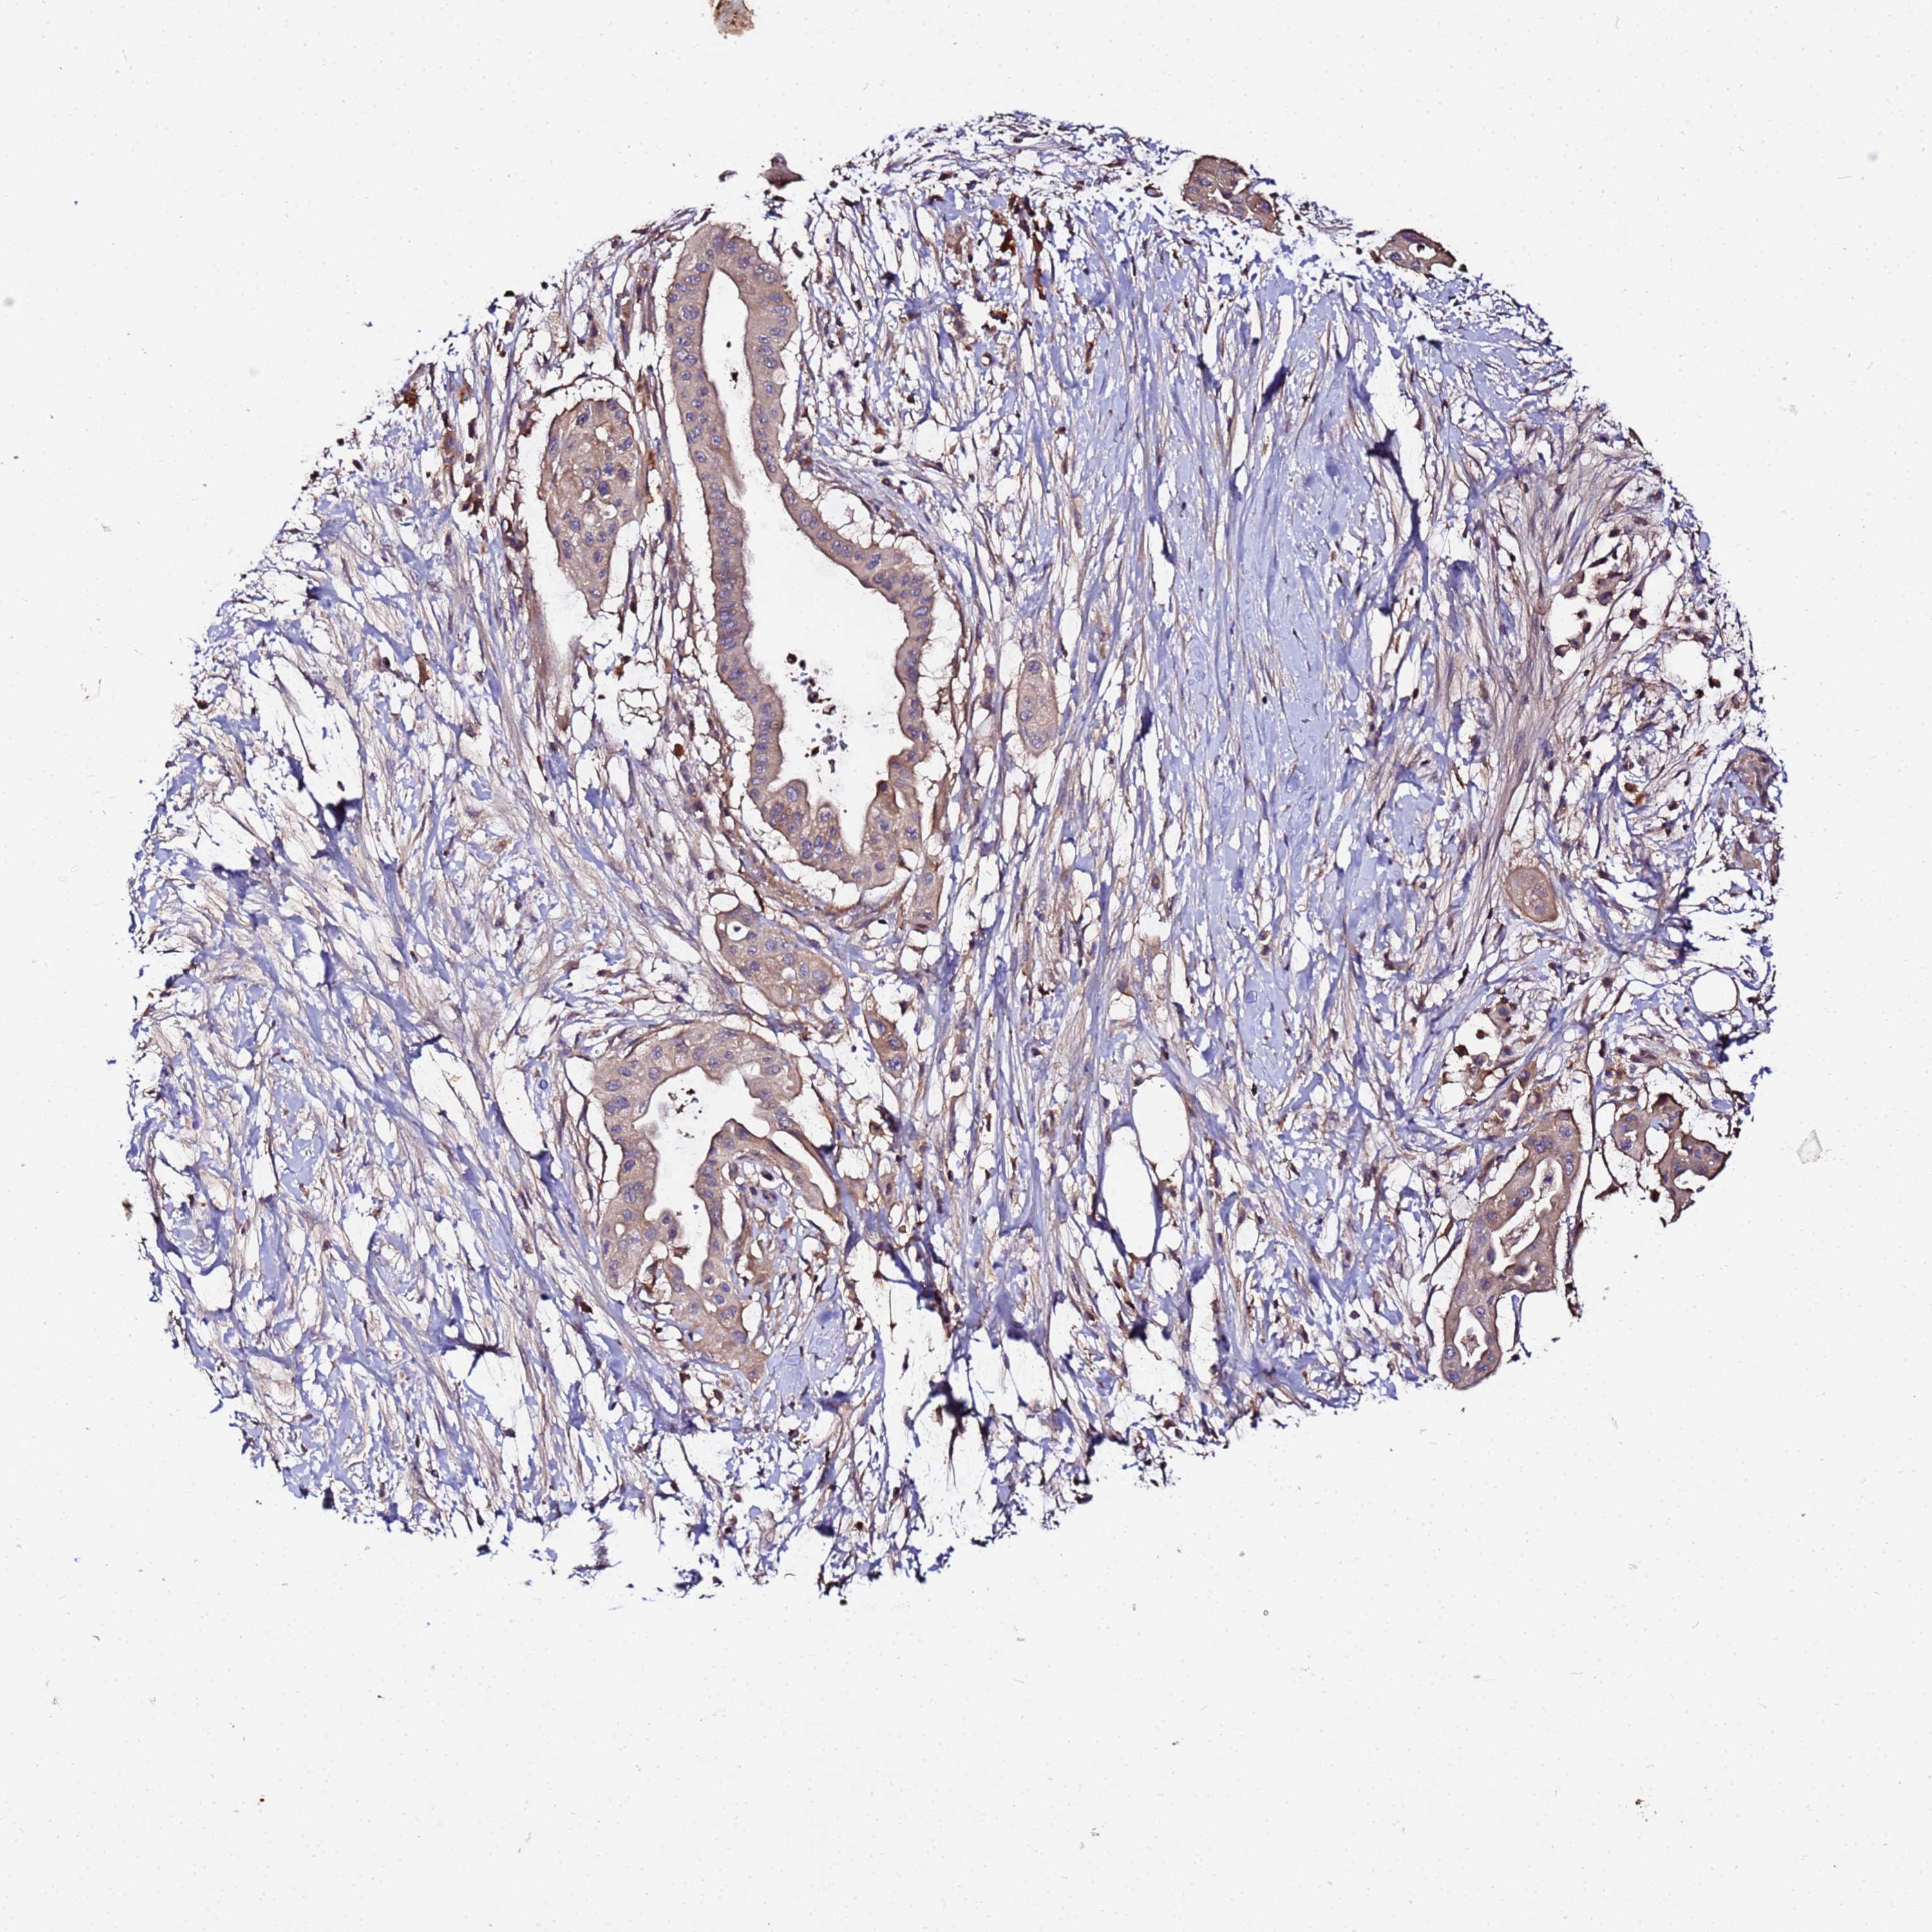

PANCREATIC CANCER - Protein expressioni

A mouse-over function shows sample information and annotation data. Click on an image to view it in a full screen mode. Samples can be filtered based on level of antibody staining by selecting one or several of the following categories: high, medium, low and not detected. The assay and annotation is described here.

Note that samples used for immunohistochemistry by the Human Protein Atlas do not correspond to samples in the TCGA dataset.

Antibody stainingi

Antibody staining in the annotated cell types in the current human tissue is reported as not detected, low, medium, or high, based on conventional immunohistochemistry profiling in selected tissues. This score is based on the combination of the staining intensity and fraction of stained cells.

Each image is clickable and will lead to virtual microscopy that enables deeper exploration of all samples and also displays staining intensity scores, fraction scores and subcellular localization as well as patient and tissue information for each sample.

Antibody HPA044894

Staining

High

Medium

Low

Not detected

Intensity

Strong

Moderate

Weak

Negative

Quantity

>75%

75%-25%

<25%

None

Location

Nuclear

Cytoplasmic/membranous

Cytoplasmic/membranous,nuclear

Adenocarcinoma, NOS